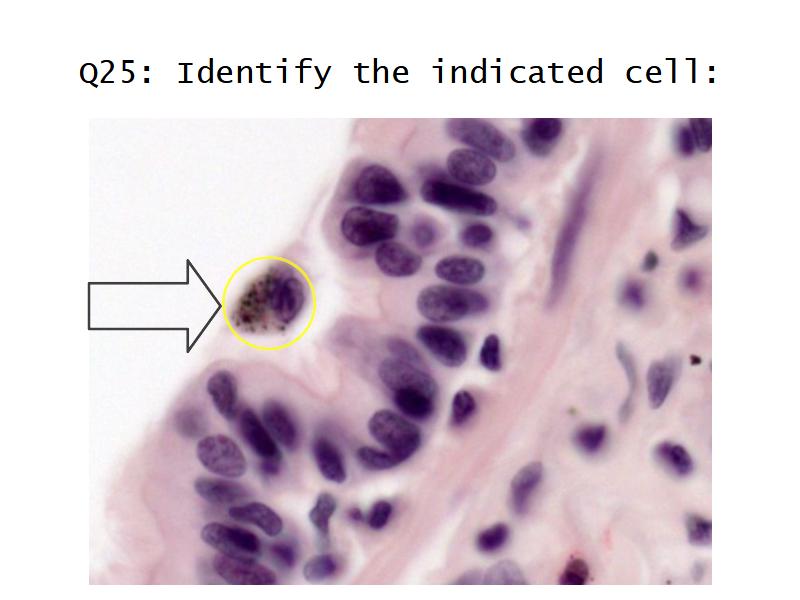

Clara cells

Read more about the use of eponyms.